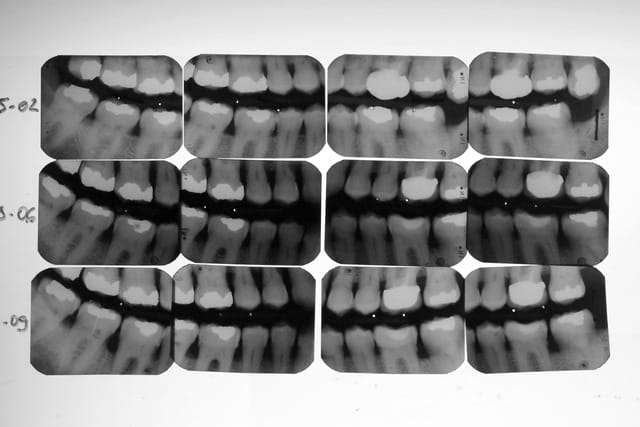

Le patient ne sait absolument pas quand son inocclusion a commencé. D’ailleurs il ne s’en était pas aperçu. J’ai mis des clichés BW de ce patient à différentes dates ( un peu floue : désolé). J’avoue ne m’être intéressé uniquement à la paro de ce patient lors des dernières consultations.